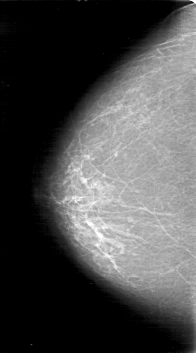

D_4047_1.LEFT_CC

RIGHT_MLO LINES 5026 PIXELS_PER_LINE 2776 BITS_PER_PIXEL 12 RESOLUTION 43.5 NON_OVERLAY